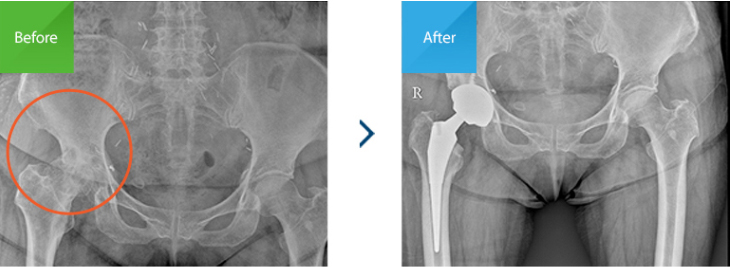

수술전 - 대퇴골두가 함몰된 모습

수술후 - 괴사로 손상된 관절을 제거하고

인공관절을 삽입함

괴사 부위가 크고 관절 손상이 심하며 통증이 극심한 고령환자의 경우에는 망가진 관절을 제거하고 인공관절을 삽입하는 인공관절치환술이 가장

합리적입니다.